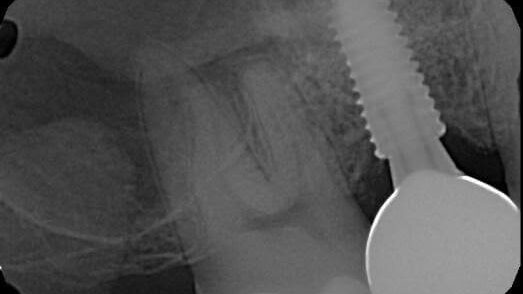

Fractured Screw in Tissue Level Implant, Unidentified System (#18i) – 0007

Dr. Mastrovich Presented on Broken Dental Implant Screw Removal at the Academy of Osseointegration, American Academy of Restorative Dentists and Dentsply PEERS Conference North America